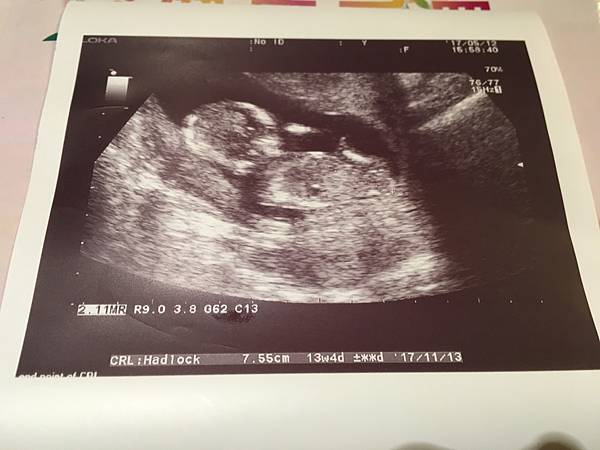

13週這天拿到了媽媽手冊跟照了超音波+

脊髓性肌肉萎縮症基因篩檢(SAM)及X染色體脆折症(FXS)自費檢查

但我對拿到媽媽手冊沒什麼感覺 (超級理性)

寶貝健健康康乖乖長大長好才是最重要的![]()